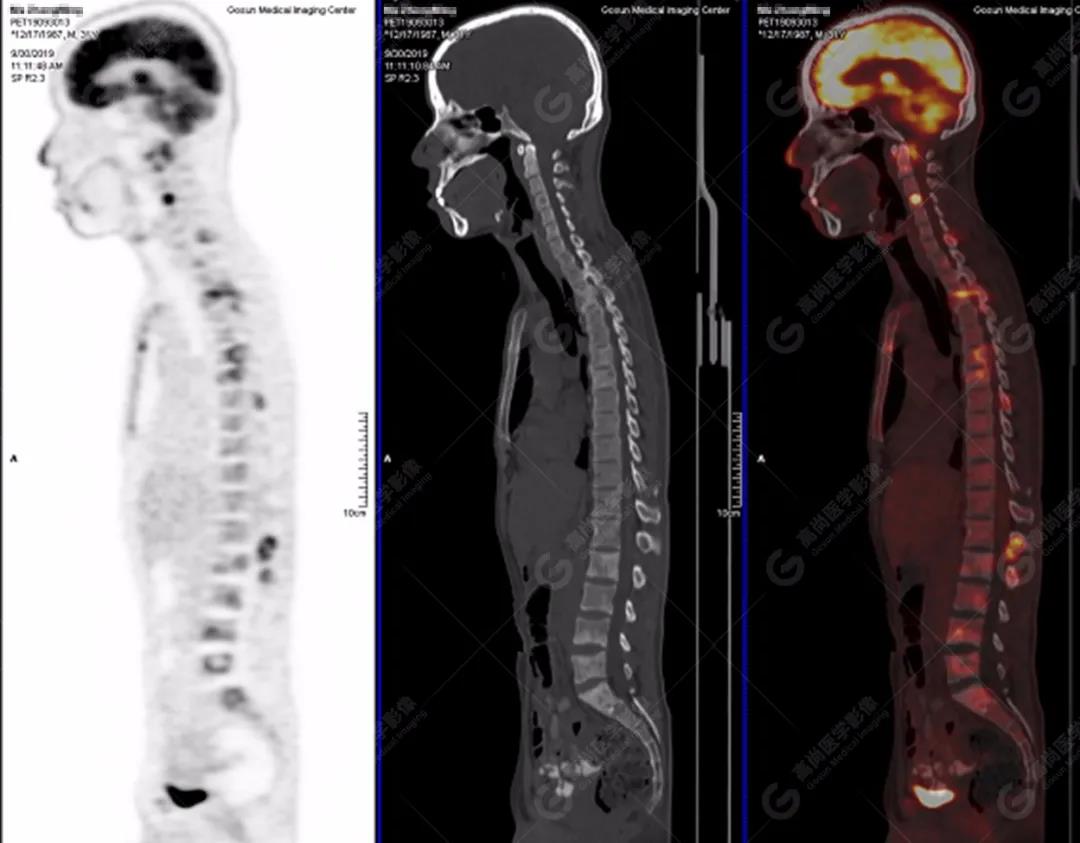

PET/CT全身圖

脊柱多發(fā)椎體及附件骨質(zhì)破壞,代謝不均性增高

全身多處骨質(zhì)破壞,代謝不均性增高

2.全身多系統(tǒng)、多形態(tài)、多發(fā)病灶(肺部、胸膜、淋巴結(jié)、骨),18F-FDG攝取不均性增高;

特征:肺部病灶簇狀分布,上葉尖段及下葉背段為著;腫大淋巴結(jié)分布不對稱,無融合、中央有壞死改變,與淋巴瘤、轉(zhuǎn)移瘤等有一定的鑒別診斷意義;

診斷意見:綜合考慮感染性病變(結(jié)核),建議相關(guān)實(shí)驗(yàn)室檢查。

本例肺內(nèi)及肺外結(jié)核,尤其脊柱結(jié)核需與轉(zhuǎn)移瘤等惡性腫瘤鑒別,18F-FDG PET/CT檢查有助于臨床排除診斷,而且可以顯示受累臟器范圍以及淋巴結(jié)分布情況。